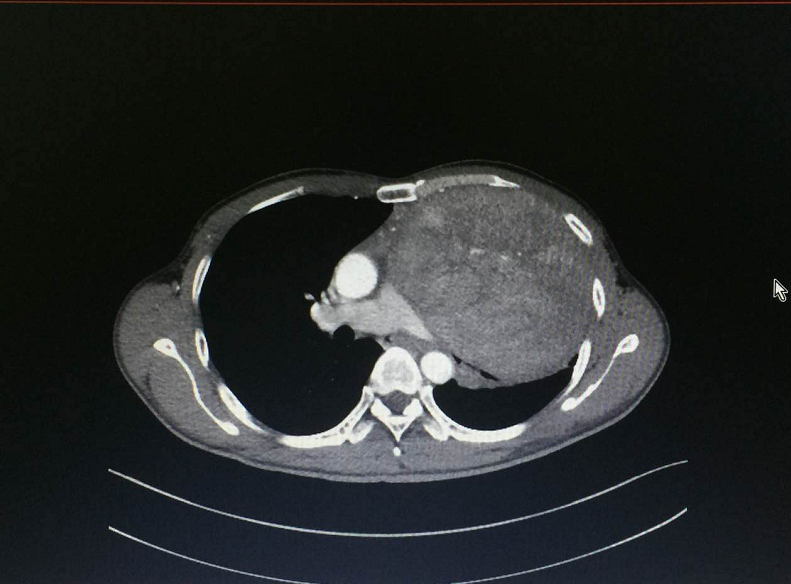

抱着试试看的心态,2017年5月初,叶先生来到港大深圳医院就诊。咋一看如此巨大的肿瘤,接诊的胸外科顾问医生庞大志同样眉头紧锁,把叶先生的胸部CT片来来回回看了一遍又一遍。庞医生告诉叶先生,这个肿瘤巨大,血供丰富,肿瘤表面有许多粗大的异生血管,与肺动脉、肺静脉、支气管等重要器官紧密相邻,心包也可能被侵犯。尽管看上去困难重重,但庞大志医生最后还是很肯定的告诉叶先生,手术治疗的机会仍然存在,可以争取完整切除肿瘤。

两个疗程的化疗结束后, CT复查的结果令人沮丧:叶先生胸腔内肿瘤没有减小,肿瘤的密度还有所增高。这意味着,只剩下手术这个治疗方案了。